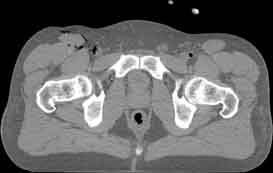

Visible Human male: Sectio transversalis 1896

CT

NMR

Pd                          / T2 \                         T1